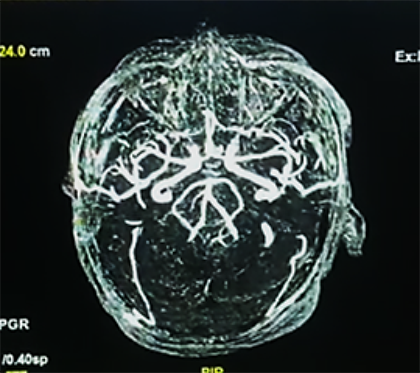

La evolución posterior se caracterizó por permanecer estable hemodinamicamente, con mejor control de la presión arterial, sin deterioro neurológico, bajo terapia de reemplazo renal; sin embargo al sexto día, en forma súbita presenta mayor deterioro neurológico con un Glasgow de 9-10/15 y mala mecánica ventilatoria, rápidamente se intuba a la paciente para protección de vía aérea, asociado a analgo-sedación; se optimizan las medidas de protección cerebral y se realiza un control tomográfico (Figura 3 a, b).